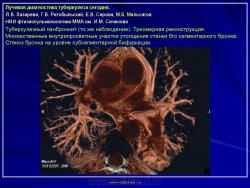

Лучевая диагностика туберкулеза сегодня

Я.В. Лазарева, Г.В. Ратобыльский, Е.В. Серова, М.Б. Мальсагов

НИИ фтизиопульмонологиии ММА им. И.М. Сеченова